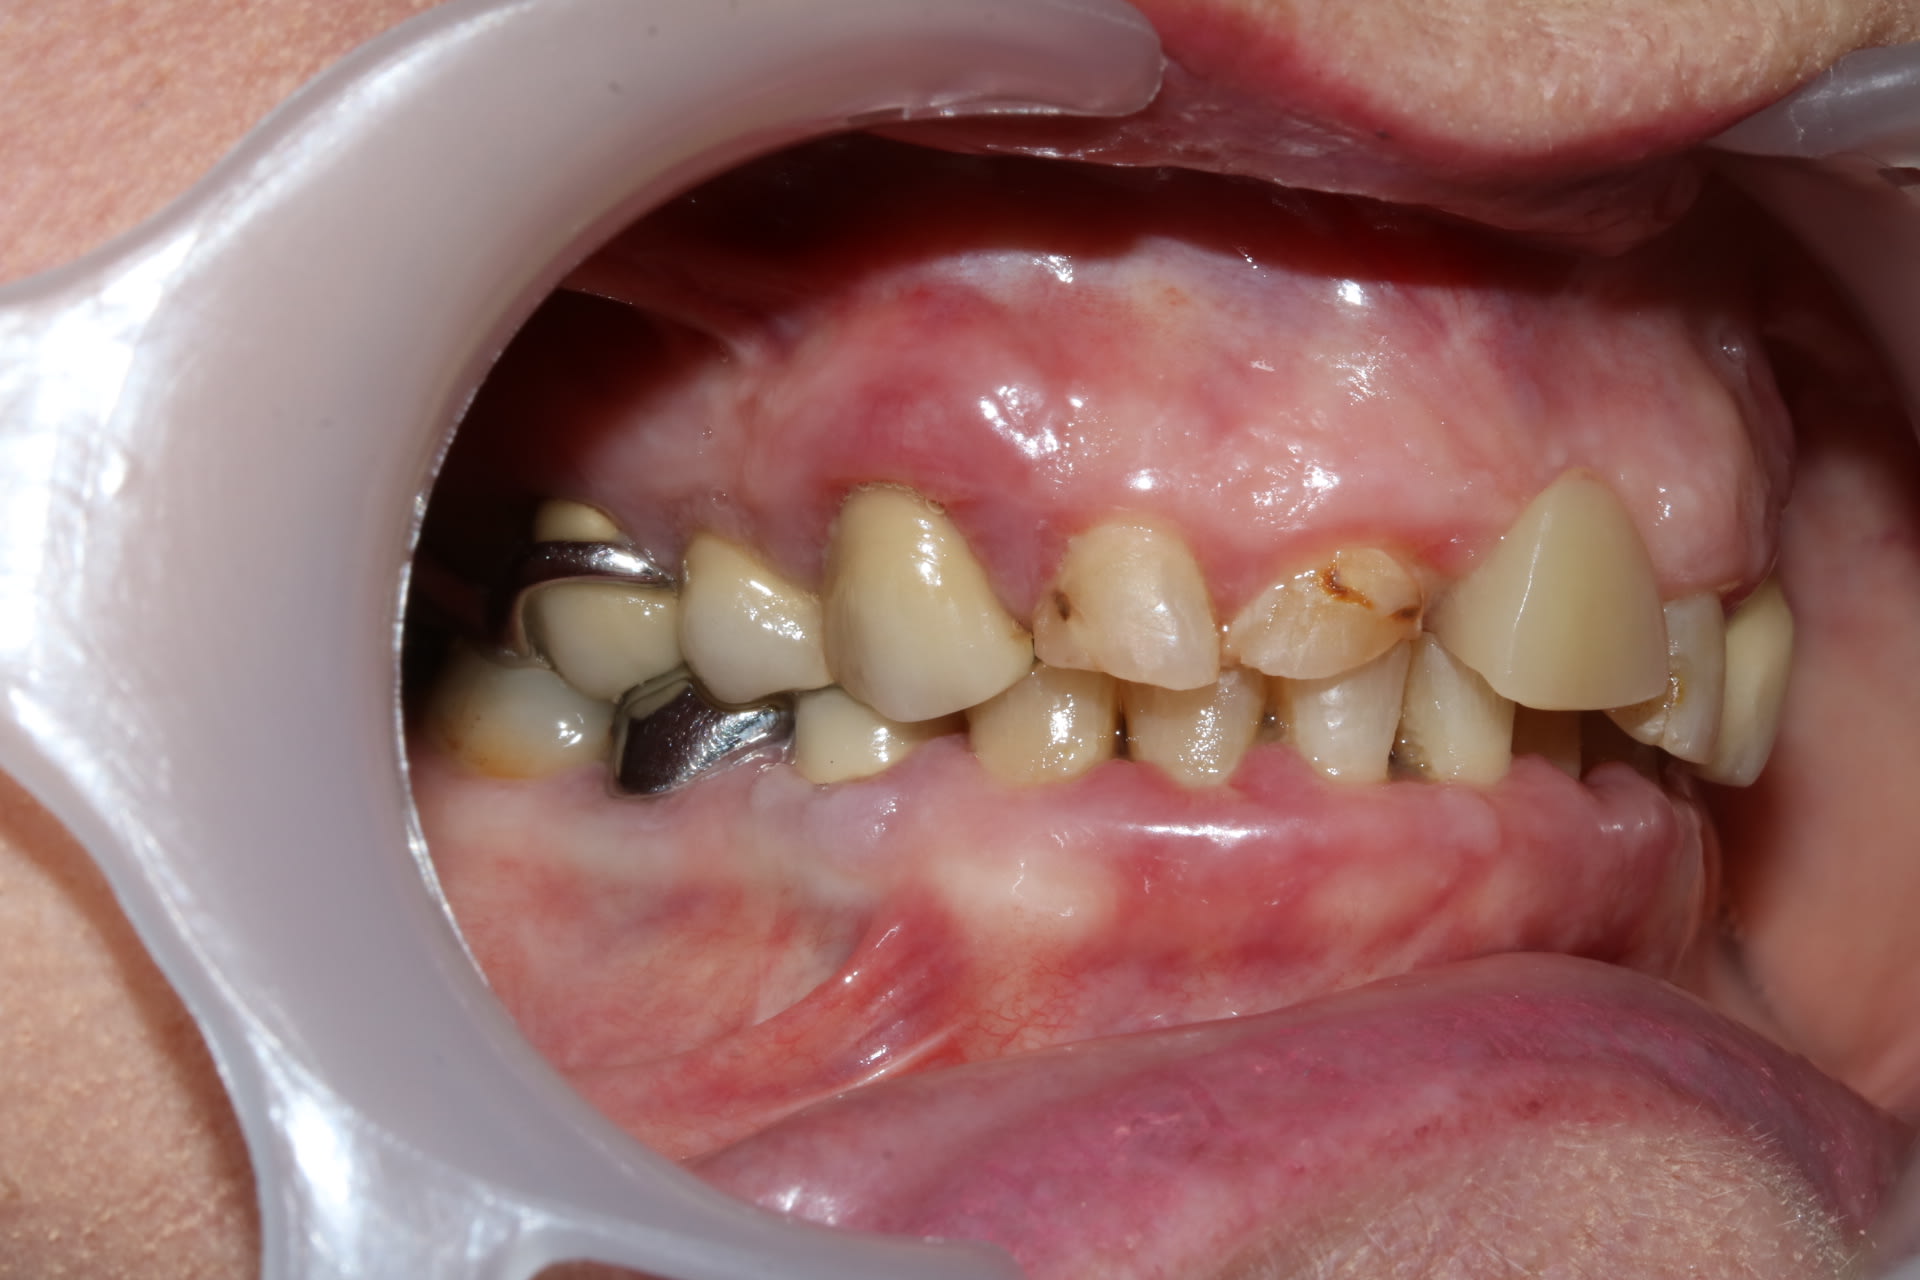

Nouvelle patiente qui vient me voir suite au départ en retraite de son ancien dentiste. Elle a conscience que c'est compliqué. Elle souhaiterait améliorer son sourire et sa mastication.

En bouche il y a un gros manque de DV, avec l’impression que tout a été reconstruit trop petit, trop bas, je ne comprend pas trop comment a été reconstruite la 23 qui semble beaucoup trop longue. Le stelite présente une particularité une selle mobile au niveau de la molaire S 2 pour "préserver la 23".

On a une mobilité 1 sur la 23.

Après en ce moment j'ai plutôt des cas qui roulent, donc un cas merdique et complexe ... c'est plutôt un challenge. Mais le truc ... C'est qu'à part raboter la 23 et à peu près tout couronner .... j'ai pas trop d’idée du plan de traitement.